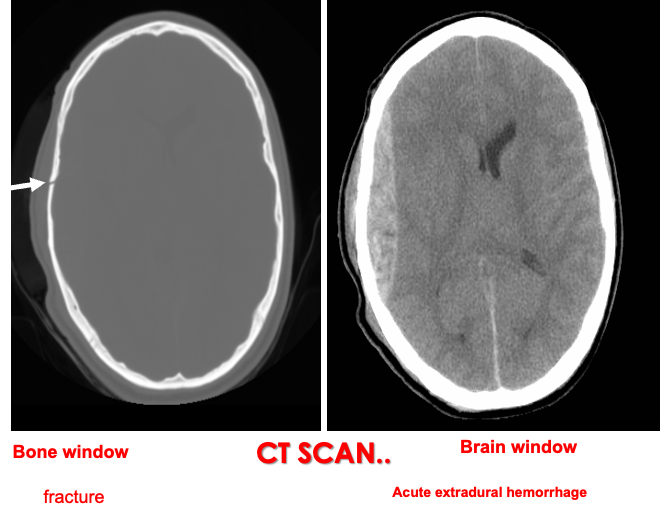

Epidural hematoma - bi-convex shape

CT without contrast axial - convex - compressed ipsilateral ventricle

bone window shoes fraction